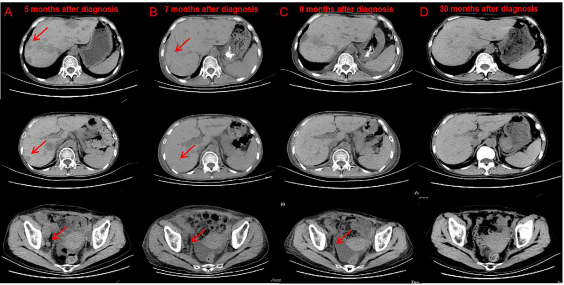

在与患者本人及其家属讨论后,给予第三疗程纳武单抗,同时定期进行血液透析。在血液透析期间,病人患上了高血压,血压高达200/120mmHg。第三疗程后两周,患者出现左腹痛,体格检查发现左肾可触及。CT扫描显示对免疫治疗有部分反应(图2 A-B),移植肾体积增加(图3 A-B)。由于患者拒绝肾活检,急性排斥反应无法得到证实。患者的体能状态下降。

图2. 纳武单抗治疗后的CT显示肿瘤缓解

图3. 移植肾的CT扫描

考虑到患者不能耐受免疫治疗,因此中断抗肿瘤治疗。通过药物治疗,高血压慢慢得到控制。第三疗程后两个月(2019年6月),CT显示免疫治疗完全有效(图2C),移植肾进一步肿胀。第三疗程后4个月(2019年8月),CT扫描显示持续完全缓解,移植肾肿胀比之前小。两个月后停用霉酚酸钠,继续使用他克莫司 0.5 mg 每天两次进行免疫抑制治疗。每三个月进行一次常规CT扫描。第三疗程后23个月(2021年3月),CT证实移植肾肿胀进一步减轻,肾脏恢复到原来的体积(图3C)。未观察到复发(图2D)。患者仍依赖血液透析。